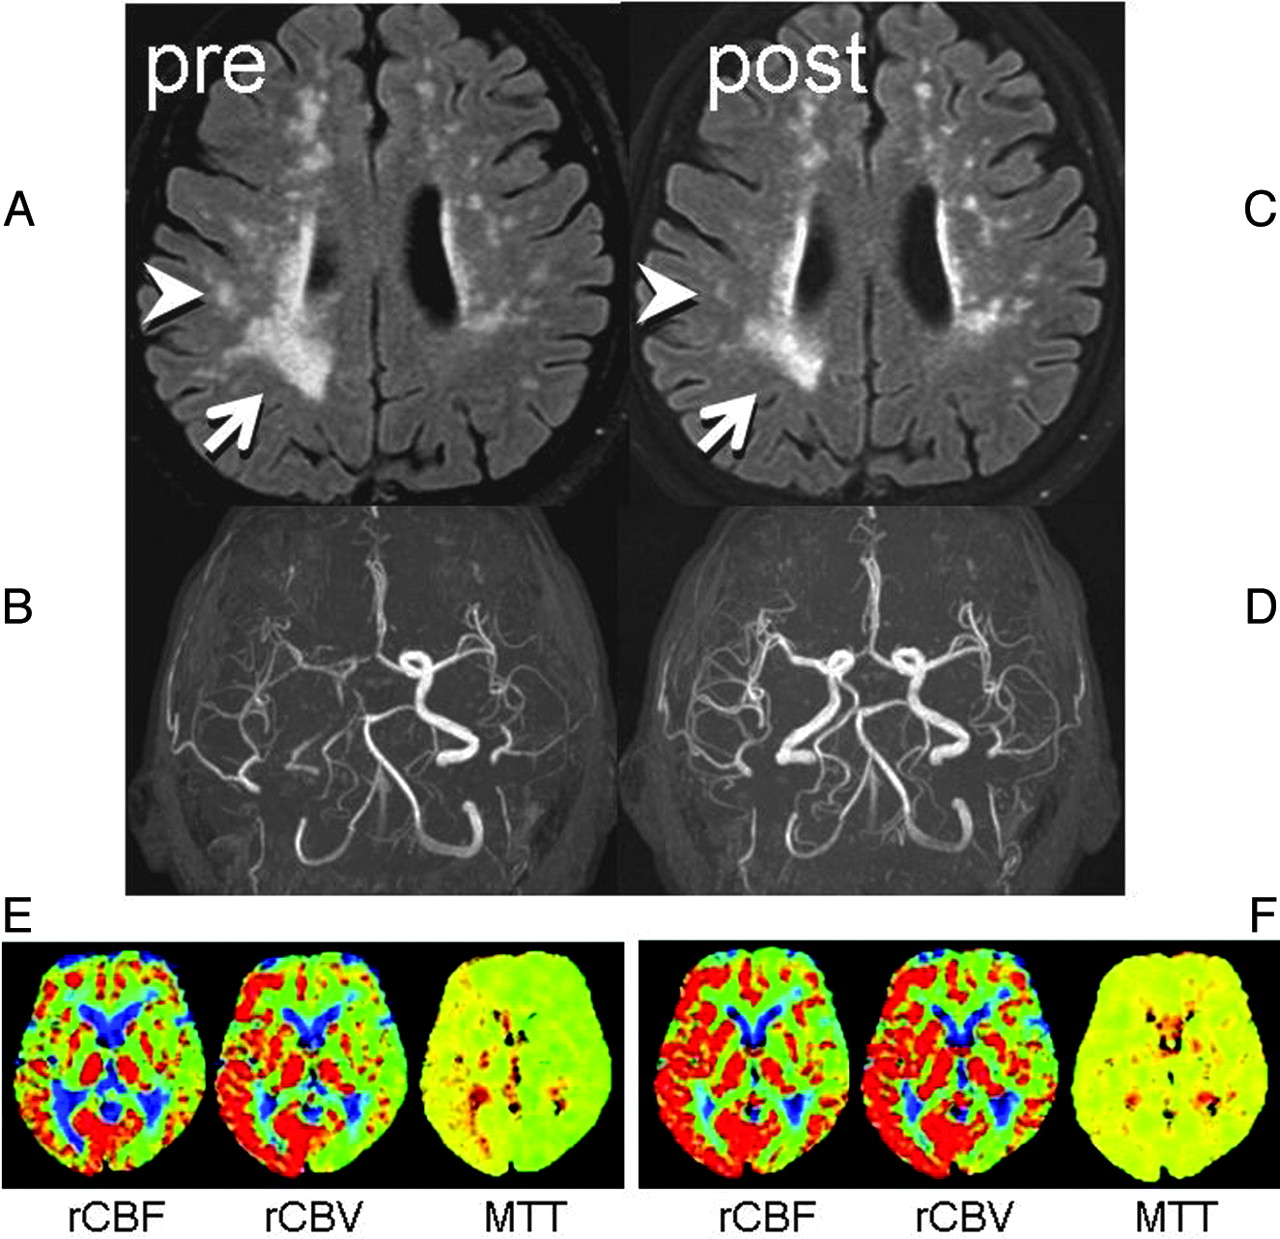

A 75-year-old man presented to our hospital with TIAs, characterized by intermittent left upper extremity weakness. DWI revealed no apparent acute infarction. Motion-sensitizing gradients of this DWI were applied to 15 different directions to enable DTI. Punctate WMLs were noted on FLAIR images at the centrum semiovale of both cerebral hemispheres, with right hemispheric laterality (Fig 1A). MR angiography revealed severe right ICA stenosis with distal flow compromise (Fig 1B).

Two consecutive FLAIR images and MR angiography. A, Preprocedural FLAIR (delay time, 2200 ms; TR/TE, 8000/100 ms) demonstrates WMLs. B, Preprocedural MR angiography (TR/TE, 30/2.3 ms) shows poor visualization of the right anterior circulation branches. C, Postprocedural FLAIR a week later shows partial WML resolution in the right hemisphere (arrow/arrowhead). D, MR angiogram shows restoration of flow in the right ICA. E, Preprocedural perfusion-weighted images show MTT elongation at the right anterior circulation territory with compensatory vasodilation, indicated by increased cerebral blood volume. F, After the procedure, the MTT elongation is normalized. Increased cerebral blood flow at the same territory indicates postprocedural hyperperfusion, but the patient remained asymptomatic.

Subsequent right carotid conventional angiography revealed pseudo-occlusion of the right ICA, with marked delay in contrast arrival at the right cerebral hemisphere. A successful stent-placement procedure was performed without any notable complications. Follow-up MR imaging 7 days after the procedure showed a patent right ICA and improvement of WMLs in the right cerebral hemisphere (Fig 1 C, -D). The patient remained asymptomatic at the recent 18-month follow-up.